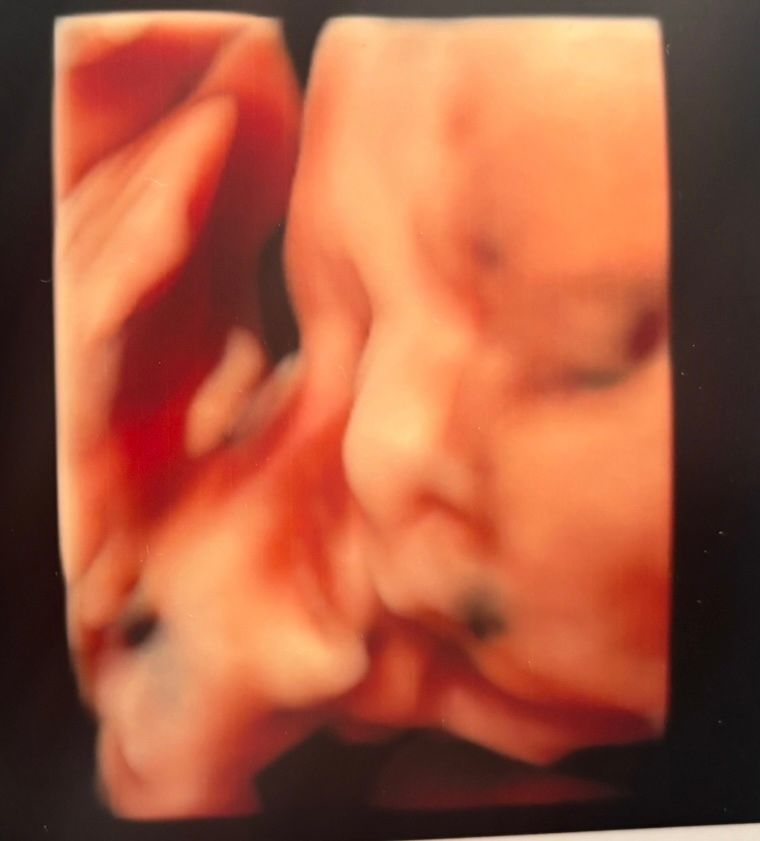

4 D узи

32н Изображение

На 30 неделе делали, сын прижался к стенке матки и еще и ручку прижал к лицу Изображение и получилось смазано, но черты лица все равно хорошо видно